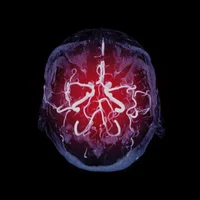

Diagnostic : le diagnostic de MCJ est basé sur les symptômes cliniques, les antécédents médicaux et des tests neurologiques. L'imagerie cérébrale, telle que l'IRM, peut montrer des changements caractéristiques dans le cerveau.